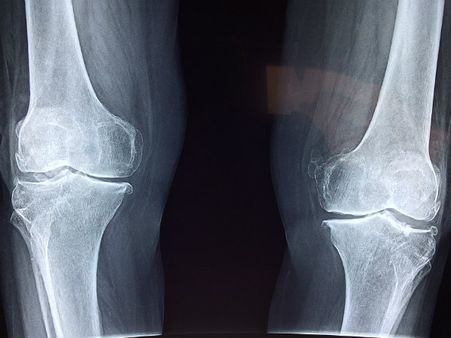

৩. হাড়ের স্বাস্থ্যের অবনতি ঘটে:

আমাদের শরীরের অন্দরে থাকা ২০৬ টি হাড় কতটা শক্তপোক্ত থাকবে তা নির্ভর করে শরীরে ভিটামিন ডি-এর যোগান ঠিক আছে কিনা তার উপর। কারণ হাড়ের স্বাস্থ্যের উন্নতির জন্য প্রয়োজনে আসা ক্যালসিয়ামের শোষণ বাড়াতে ভিটামিন ডি বিশেষ ভূমিকা পালন করে থাকে। এই কারণেই তো এই ভিটামিনটির ঘাটতি দেখা দিলে নানাবিধ হাড়ের রোগ মাথা চাড়া দিয়ে ওঠে। সেই সঙ্গে পিঠে, পায়ে এবং পাঁজরে যন্ত্রণা হওয়ার মতো লক্ষণ দেখা যায়।